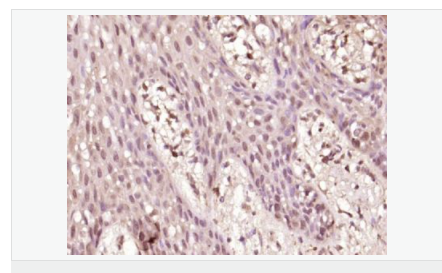

產品應用WB=1:500-2000 ELISA=1:5000-10000 IHC-P=1:100-500 IHC-F=1:100-500 Flow-Cyt=1μg /test IF=1:100-500 (石蠟切片需做抗原修復)